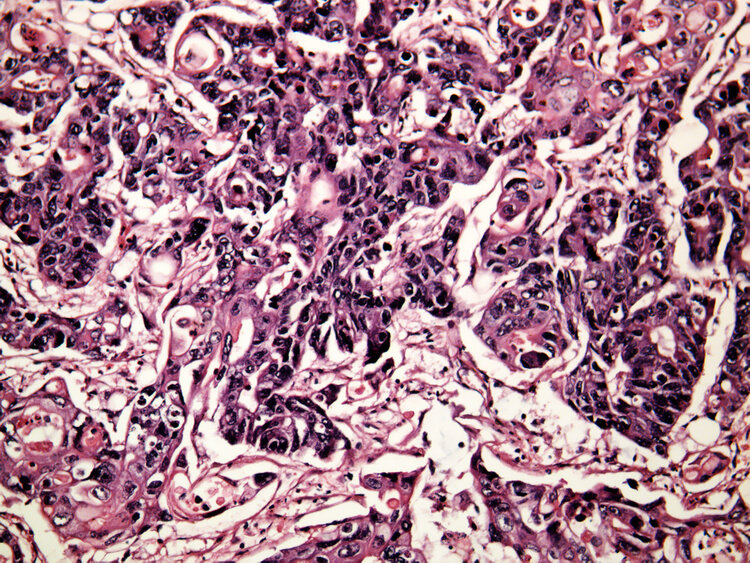

质子治疗是先进的肿瘤放射手段之一 , 利用看不见摸不着但可以被电磁场精确控制的质子来杀灭肿瘤 。

试验结果表明 , 参与试验的患者在经过质子治疗后 , 肿瘤的症状、体征以及标志性肿瘤指标均得到了明显改善 , 肿瘤控制率达到了100% , 接近一半的患者治疗后病灶完全消失、一成受试者病灶明显缩小 。 并且质子治疗有效减少了患者身上可能出现的副作用 , 生活质量得到了很大提升 。

传统放疗在穿透皮肤和到达肿瘤时一直都在释放辐射 , 在这个过程中很可能会破坏周围正常组织和器官 。 质子治疗则可根据能量的大小在某个深度形成剂量高峰 , 能量释放主要集中在肿瘤部位 , 皮肤以及身体的其他位于肿瘤前方正常组织受到的辐射剂量较小 , 肿瘤后方的组织受到的剂量几乎为0 。